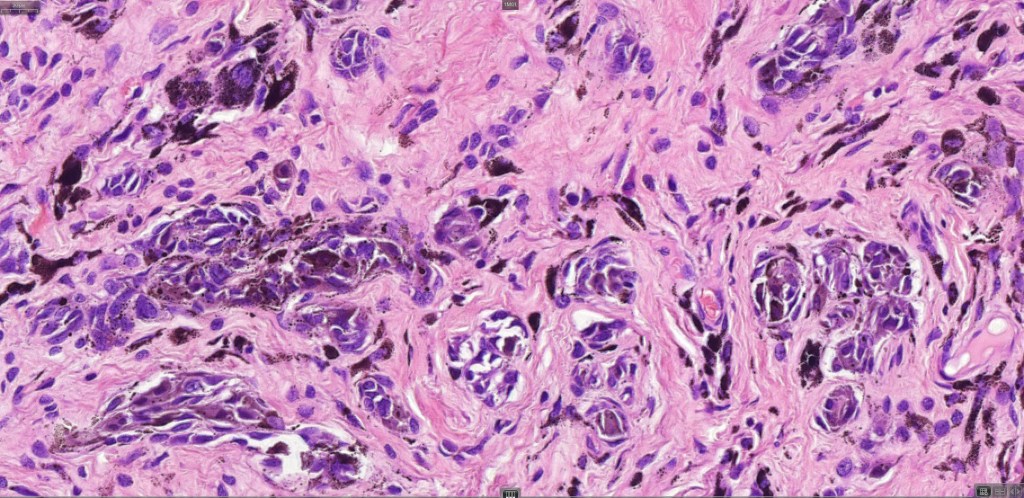

This is uncommon and presents clinically with a history of recent change in color of a common or less often congenital nevus causing concern for melanoma by the clinician. Some, but not all are probably deep penetrating and combined nevus variants. Others may represent follicular type-A cell nests. It is characterized by the presence of deep nest(s) of type -A nevus cells surrounded by & with overlying type-B nevus cells.